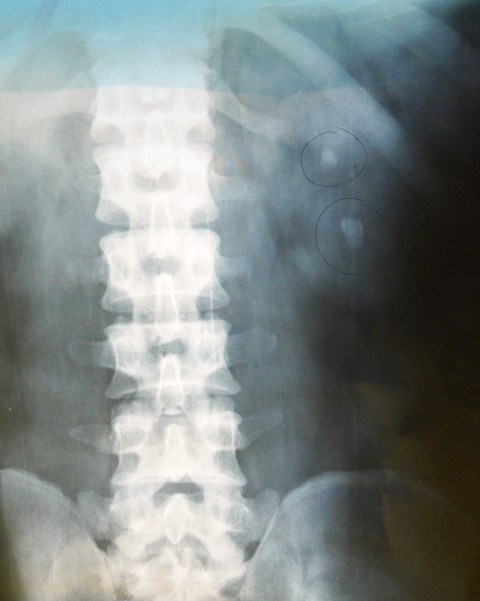

Radiologi BNO : gambaran radioopak di ren sinistra 2x1 cm dan 1x1 cm

Radiologi BNO gambaran radioopak di Vesika Urinaria ukuran 2x1 cm, 0,5x0,5 cm dan 1x1 cm.

Foto Polos Abdomen/ BNO dapat membantu menegakan diagnosis adanya batu ginjal tetapi apabila batu tersebut terdiri dari batu kalsium atau batu struvite, sedangkan apabila batu tersebut terdiri dari batu asam urat maka pemeriksaan penunjang yang terbaik adalah CT Scan. Pada pasien ini sebaiknya dilakukan pemeriksaan Pielografi Intravena tetapi karena keterbatasan biaya, alat dan tenaga ahli maka hal ini tidak dilakukan.

3 bulan setelah menjalani terapi dan keluhan berkurang masih ditemukan batu di vesika urinaria, hal ini bisa menggambarkan adanya pembentukan batu yang baru, tetapi karena berdasarkan teori biasanya batu yang baru terbentuk setelah 2-3 tahun, maka kemungkinan adalah batu dari ginjal yang sudah bergeser ke vesika urinaria. Untuk memastikan jumlah batu sebaiknya pasien dirujuk ke Rumah Sakit dengan Instalasi Radiologi lebih lengkap disertai Dokter Ahli Radiologi untuk dilakukan pemeriksaan Pielografi Intravena.